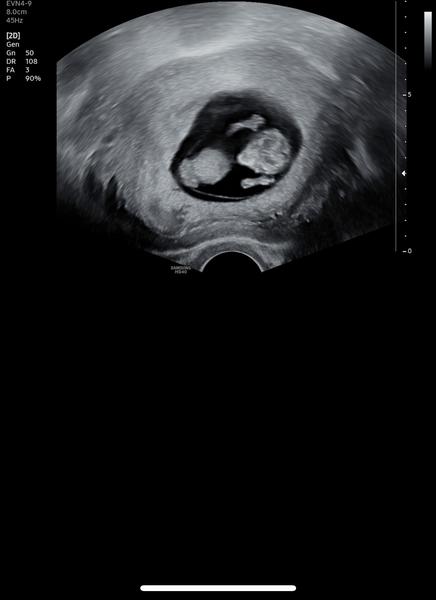

@maaaadlaaaaa Takhle dneska na nás mával pri UZ.

@kate4597 😂 povedený ultrazvuk, přeji hodně štěstí. Jinak já ten sirup brala jen když jsem opravdu nemohla zabrat a hlavou se mi honilo bůhví co a jen večer. Za celé těhotenství jsem využila tak půl lahvičky.